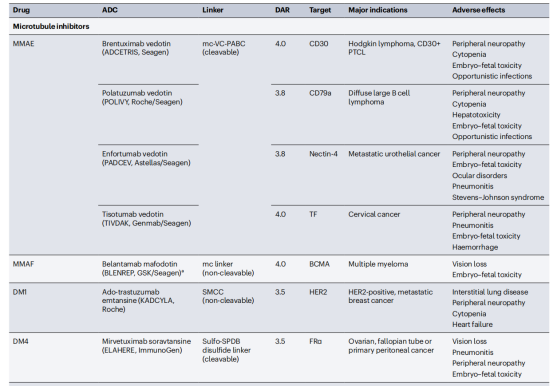

偶联抗体包括抗体药物偶联物(ADC),免疫毒素,放射性同位素相关联的抗体,这些抗体增强了抗体杀死细胞的能力。ADC是通过将肿瘤靶向抗体与细胞毒性药物连接而构建的。ADC分子与细胞表面抗原结合导致其内化,然后在细胞内释放细胞毒性药物。这允许选择性地将细胞毒性药物递送到癌细胞,同时保留大多数健康组织。ADC的关键成分包括肿瘤靶向抗体、细胞毒性药物和连接抗体与细胞毒性药物的连接体。部分ADC药物已显示出显著的临床成功,选择性地向癌细胞递送强效细胞毒性药物。